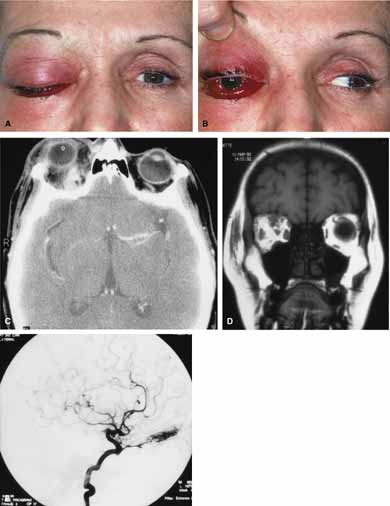

Arterial flow malformations are distinguished by evidence of arterial flow. The primary examples are arteriovenous malformations that have a direct flow from the arterial side, through a malformation, and then to the venous side of the circulation. Arteriovenous malformations are characterized by high arterial flow directly into the anomaly that exits through the normal venous channels, which may arterialize. Thus, they bypass the orbital system and more commonly act to shunt blood away from rather than into normal vascular channels.59 Clinically they are associated with pulsating exophthalmos or recurrent episodes of hemorrhage or thrombosis (Fig. 11A and 11B). They are often associated with a bruit (which may be heard by the patient) and may cause pain when engorged with straining or Valsalva maneuver. With imaging, orbital arteriovenous malformations are characterized by irregular, rapidly enhancing masses that may have high flow characteristics on Doppler studies and flow voids on MRI scanning (Fig. 11C, 11D, and 11E). Direct selective angiography will demonstrate the engorged, rapidly filling proximal arterial system, the malformation and the distal venous outflow. Management may involve selective gluing followed by excision. For those lesions with feeding vessels that are outside the orbit, a direct cut-down followed by embolization and surgery is also a safe and direct approach.59

Fig. 11 A. A 48-year-old female presented with sudden proptosis (developing over several minutes), pain, ptosis, decreased ocular motility, decreased visual acuity, and conjunctival chemosis. B. Conjunctival chemosis and restricted motility is seen. C. On axial computed tomography (CT) scanning a contrast enhancing mass is seen superiorly. D. Coronal magnetic resonance imaging (MRI) scanning revealed the superior anomaly. E. Angiography demonstrated an arteriovenous malformation of the right orbit. The vascular malformation was successfully removed surgically.